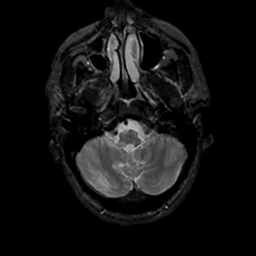

MR Study #17, July 7, 1991 -- Slice #8

[Home][Help][Clinical][Tour 1][Tour 2] Slice 8